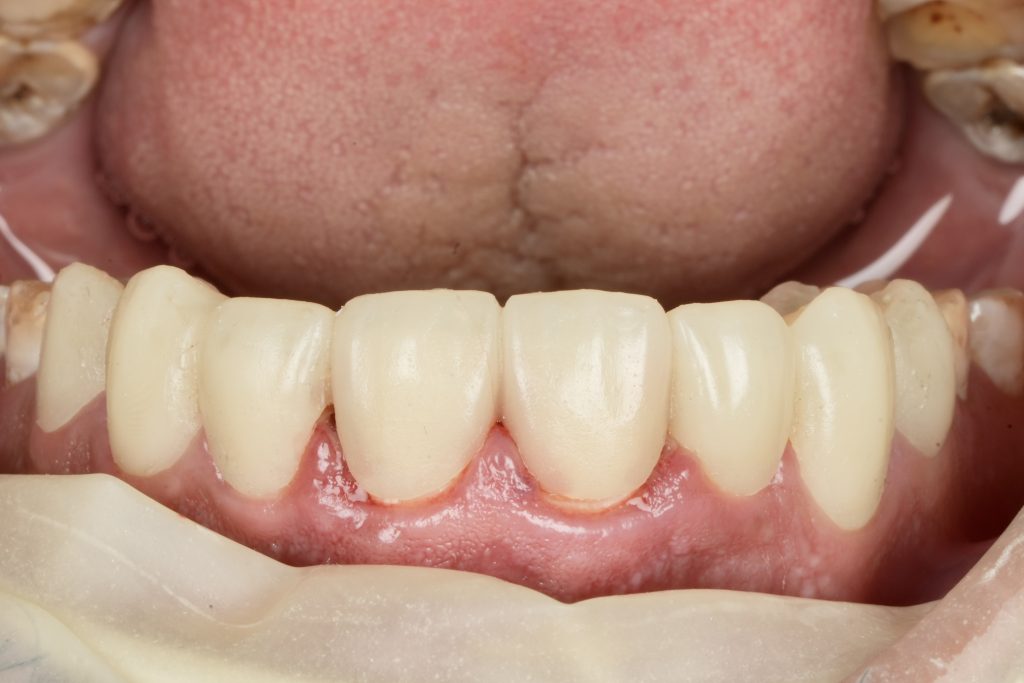

IPS E-max Press veneers were pressed and characterized using micro-layered incisal ceramics for vitality and translucency. Surface texture and internal effects were customized to simulate natural perikymata and halo zones (Fig 3).